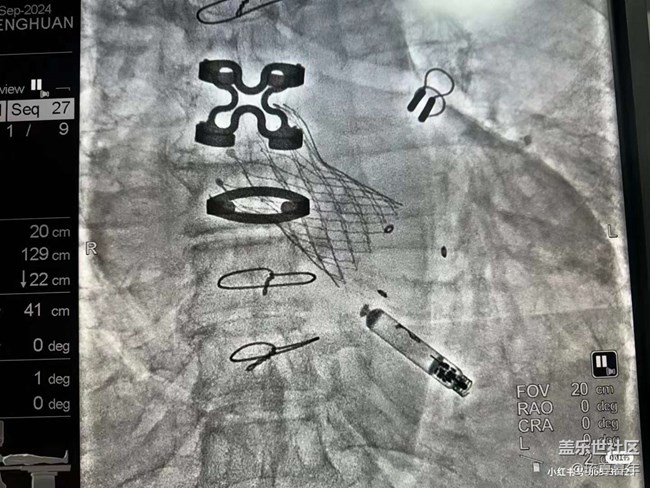

价值一套房子的心脏,大家能认出来吗